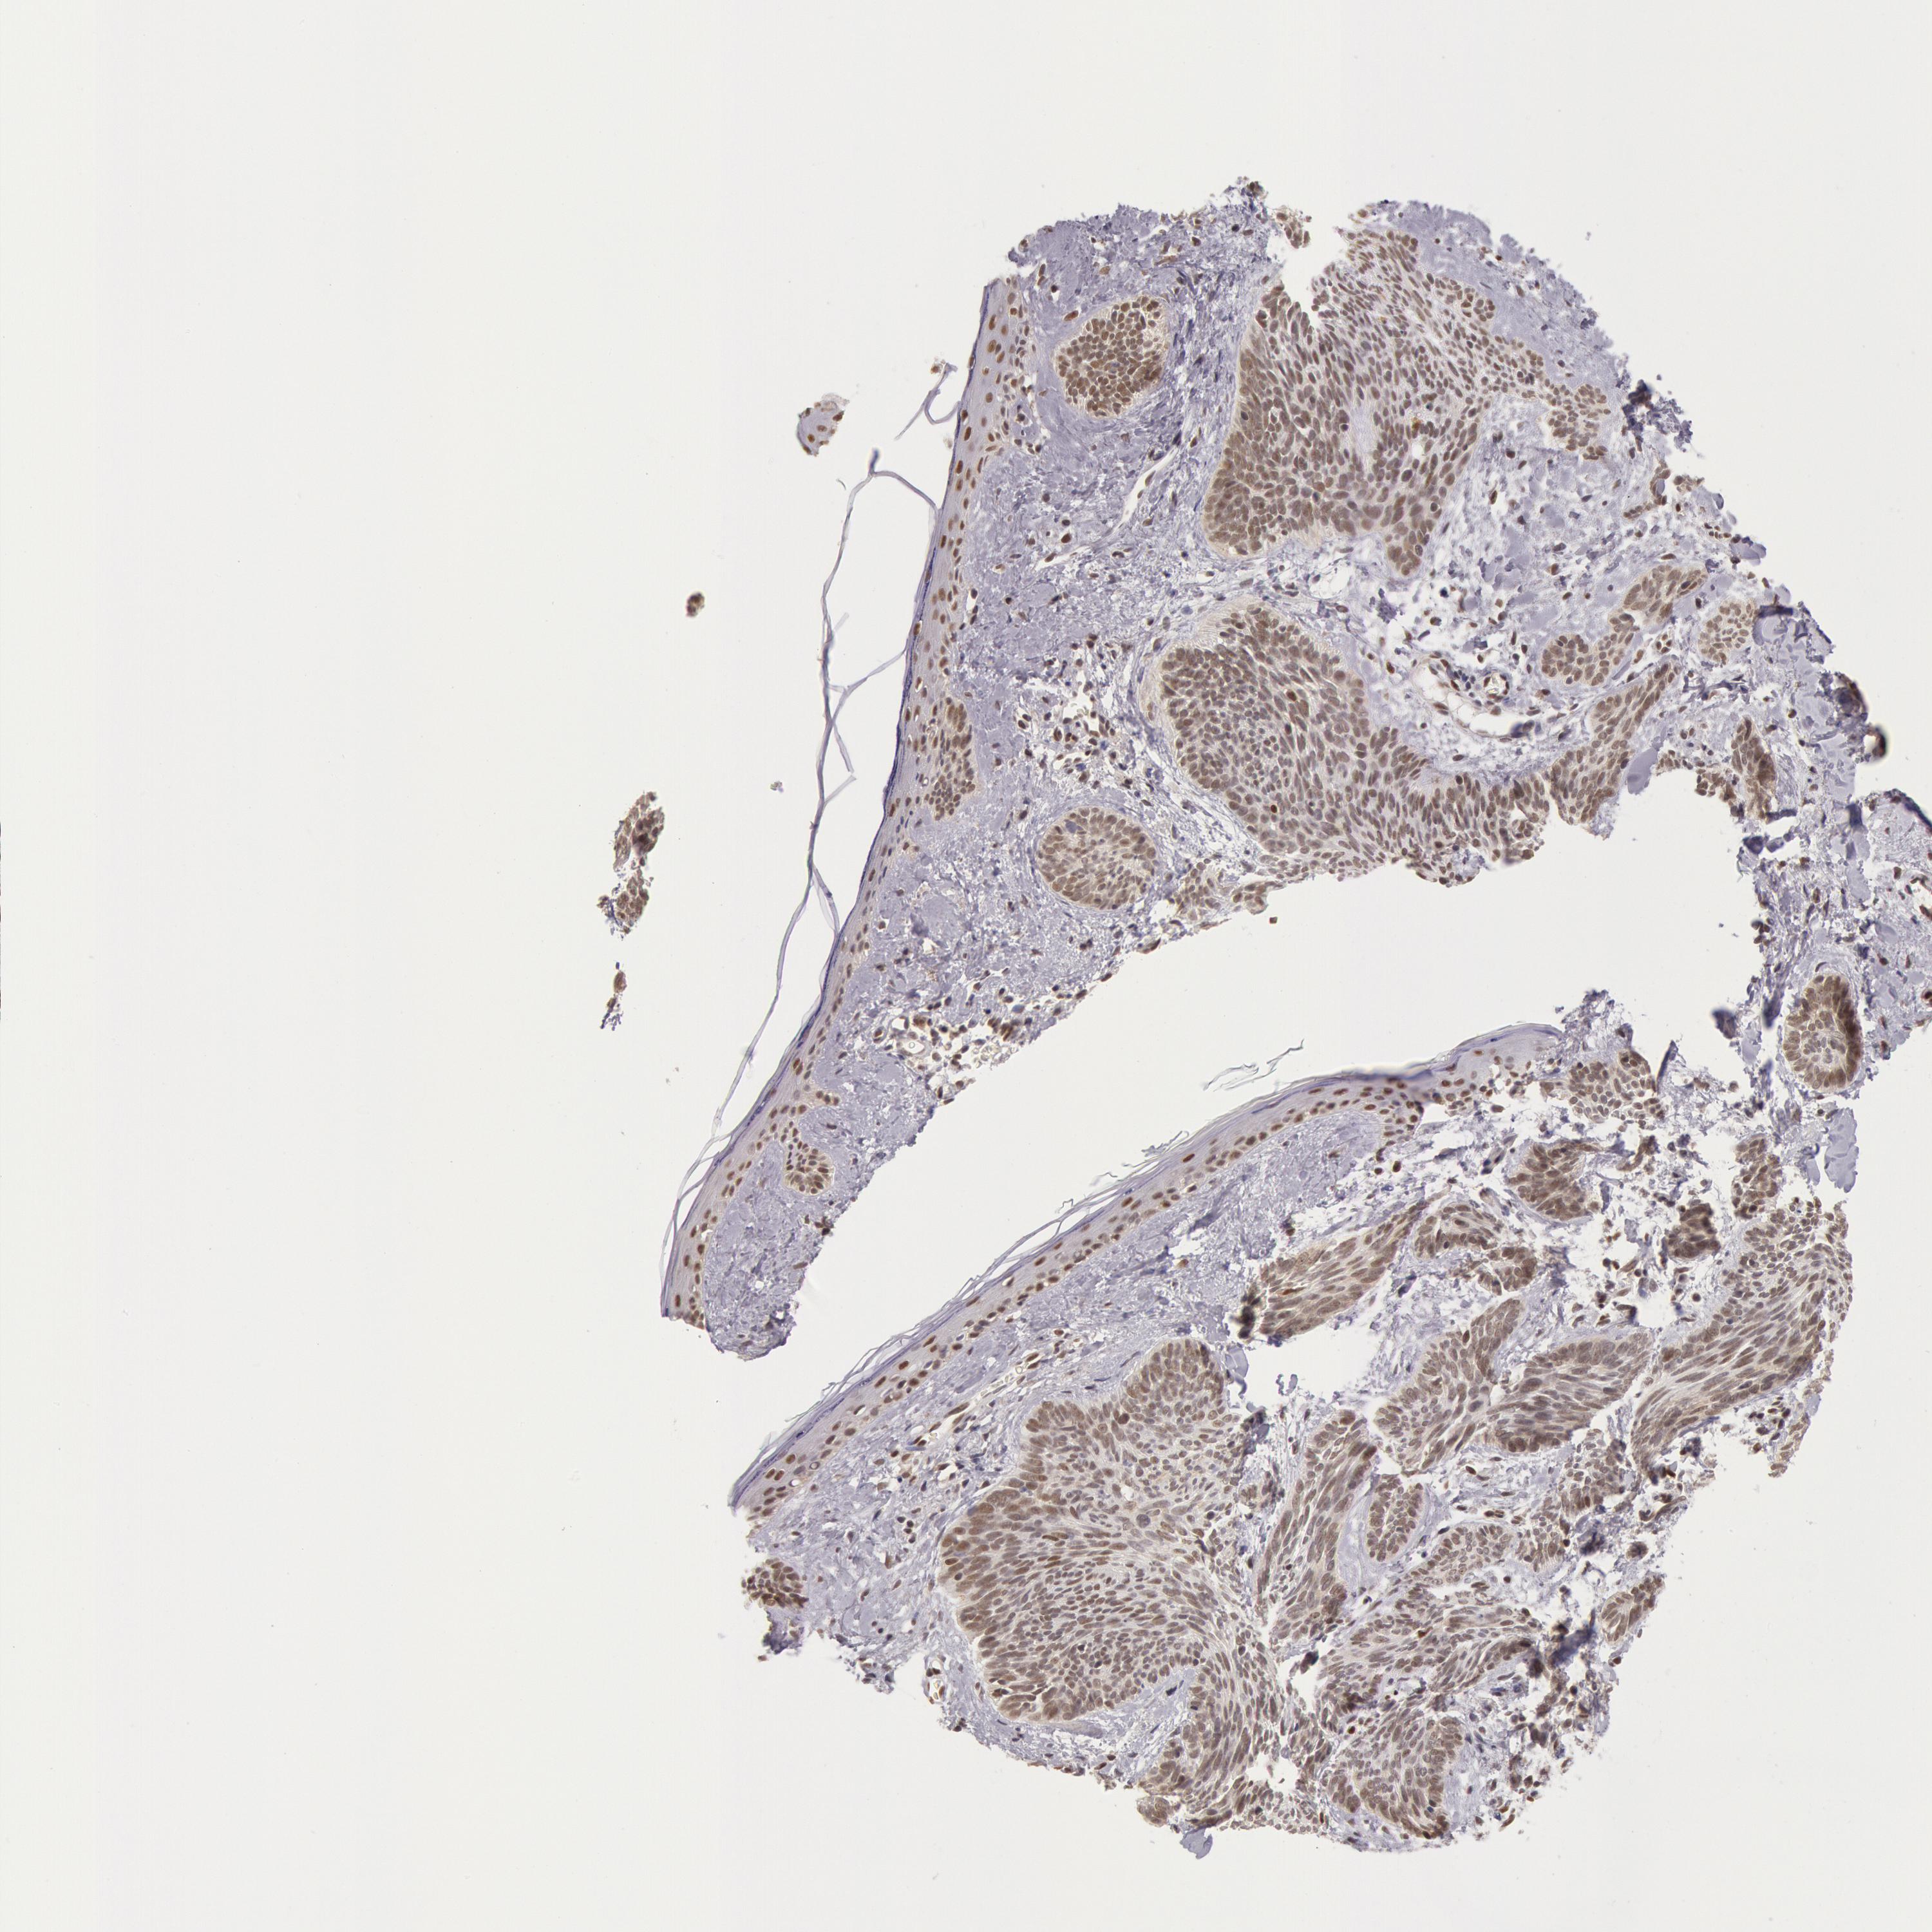

SKIN CANCER - Protein expressioni

A mouse-over function shows sample information and annotation data. Click on an image to view it in a full screen mode. Samples can be filtered based on level of antibody staining by selecting one or several of the following categories: high, medium, low and not detected. The assay and annotation is described here.

Each image is clickable and will lead to virtual microscopy that enables deeper exploration of all samples and also displays staining intensity scores, fraction scores and subcellular localization as well as patient and tissue information for each sample.

Antibody HPA001221

Antibody HPA001222

Staining

High

Intensity

Strong

Quantity

>75%

Location

Nuclear

Squamous cell carcinoma, NOS

Basal cell carcinoma